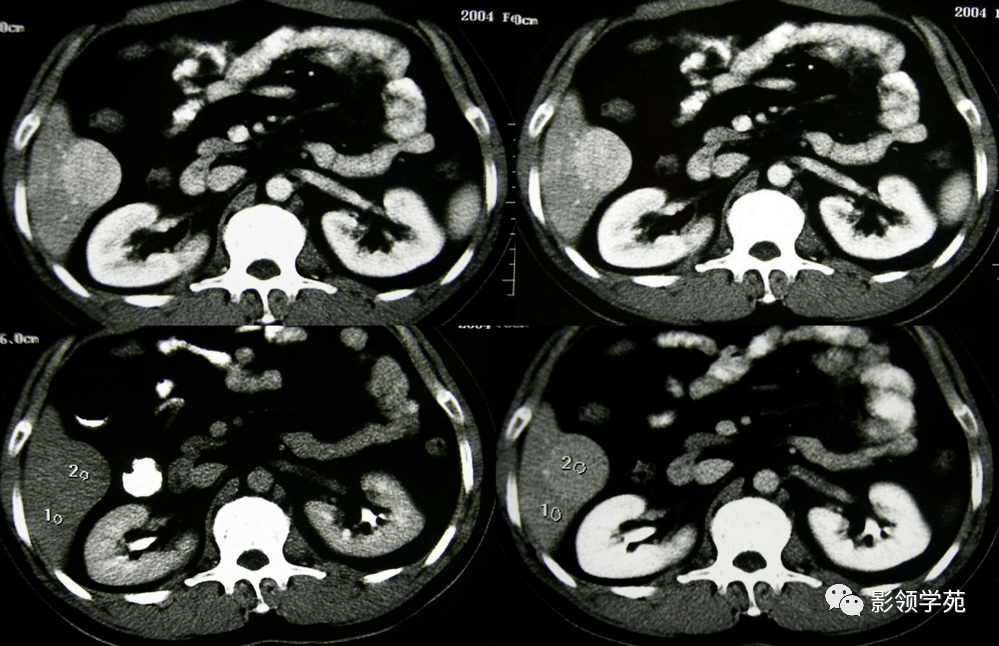

肝脏炎性假瘤的影像表现

图片尺寸960x720